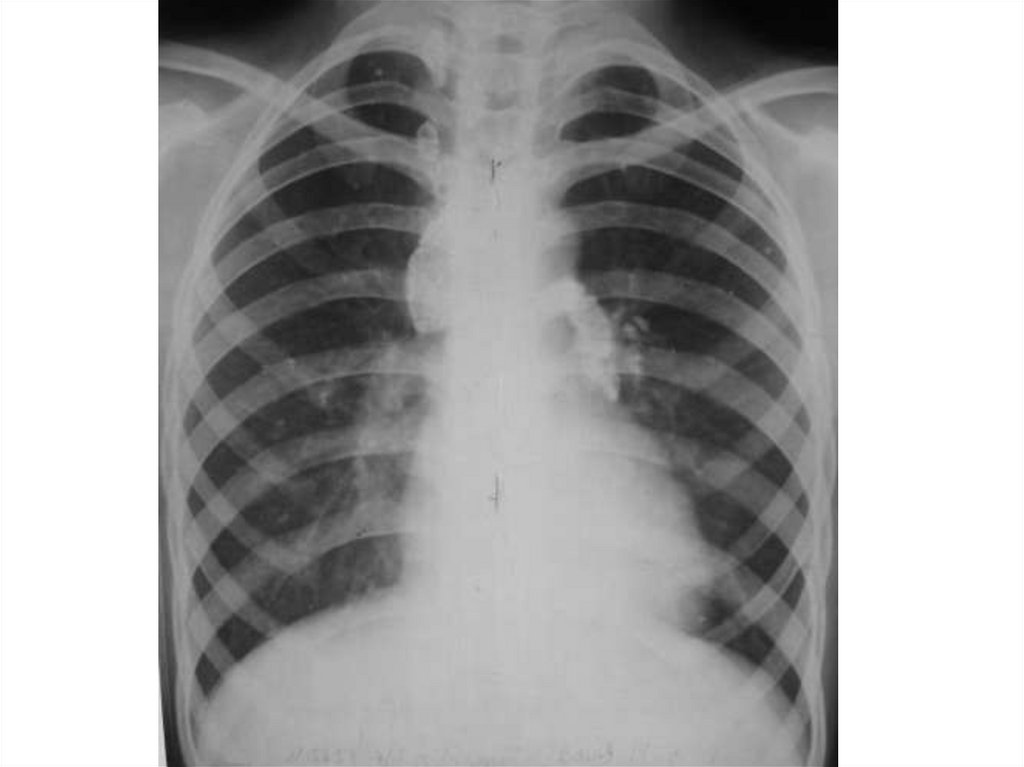

Пневмония